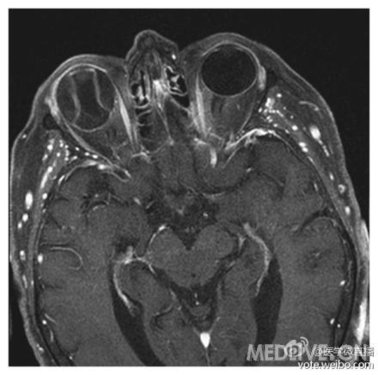

视网膜剥离

磁共振成像显示右眼可见视网膜剥离,对称隆起异常。